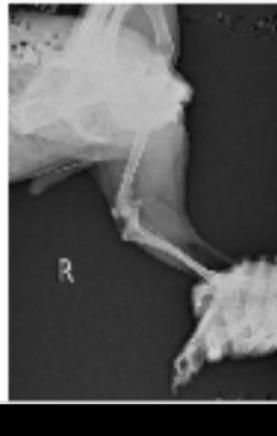

- 반려동물 건강반려동물순박한개개비238강아지 엑스레이 슬개골 탈구랑 십자인대 봐주세요ㅠㅠ저희집 강아지가 공놀이를 좋아하고 산책할때 좀 흥분해서 뛰는 편입니다ㅠㅠ 그래서 어릴때부터 슬개골이 좋지는 않고 1기에서 2기로 진행되고 있다는 얘기는 왕왕 들었는데 항상 꼬리를 들고 있는 앤데 꼬리도 내려가고 오른쪽 다리를 아파하는거 같고 산책나가서도 앉고 안걸을려고 해서 병원을 갔는데 슬개골 탈구랑 십자인대도 좀 안좋은거 같다고 영상기기 있는 곳애 가보라고 하셔서 가서 엑스레이를 찍어봤습니다..근데 그 병원에서는 슬개골이 안좋긴한데 삔거 같다고만 하셔서 약을 받아왔는데 그 뒤로 강아지가 꼬리를 드니깐 화들짝 놀라면서 싫어하는거 같더라구요...그래서 또 다른 병원을 갔느데 거기에는 또 영상기기가 없는데 슬개골탈구다 수술해야한다고만 얘기하셔서 혼란스럽네요ㅠㅠㅠ엑스레이 한번만 봐주실 수 있나요ㅠㅠ그리고 다리가 안좋을때 꼬리를 들면 다리가 더 아플 수 있나요?? 아니면 그냥 아파서 꼬리가 내려간걸까요...?? 후자면 다행인데 사람이 살살 들어봤을때 아파하는거 같아 허리 디스크에도 뮨제가 있는건 아닌지 걱정이 됩니다...ㅠㅠㅠㅠ1명의 전문가가 답변했어요